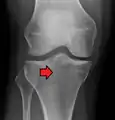

Lipohemarthrosis (presence of fat and blood from bone marrow in the joint space after an intraarticular fracture) seen on X-ray in a person with a subtle tibial plateau fracture

Lipohemarthrosis due to a tibial plateau fracture

Subtle tibial plateau fracture on an AP X ray of the knee

A tibial plateau fracture seen on X-ray